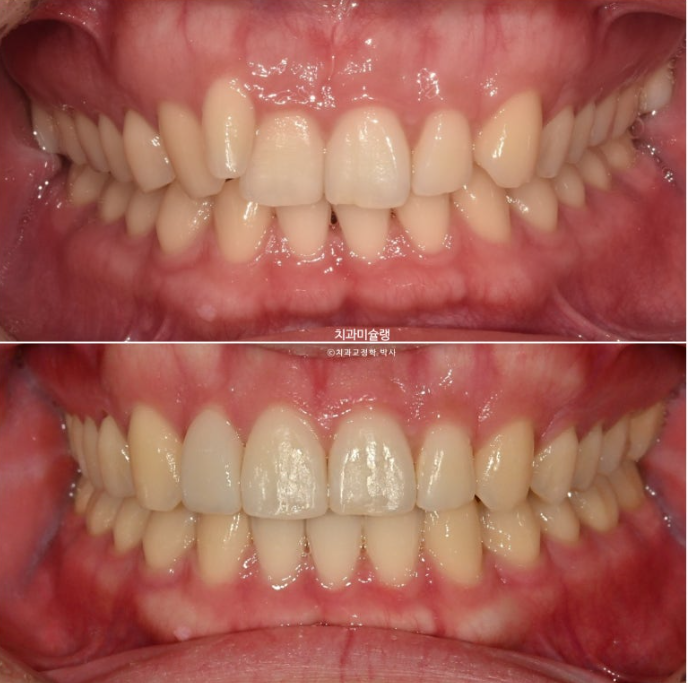

아래 앞니 블랙트라이앵글은 치축의 개선과 소량의 치간삭제로 사이즈를 줄였습니다.

치료 전 후 파노라마 엑스레이를 보면 블랙트라이앵글의 원흉이었던 아래 앞니 치축 기울어짐이 해소된게 보입니다.

위 앞니 치축도 평행해졌습니다.

<인비절라인으로 뿌리 이동은 안된다.>는 잘못된 말입니다.

1년 8개월간의 치료 기간동안 치근흡수는 없습니다.